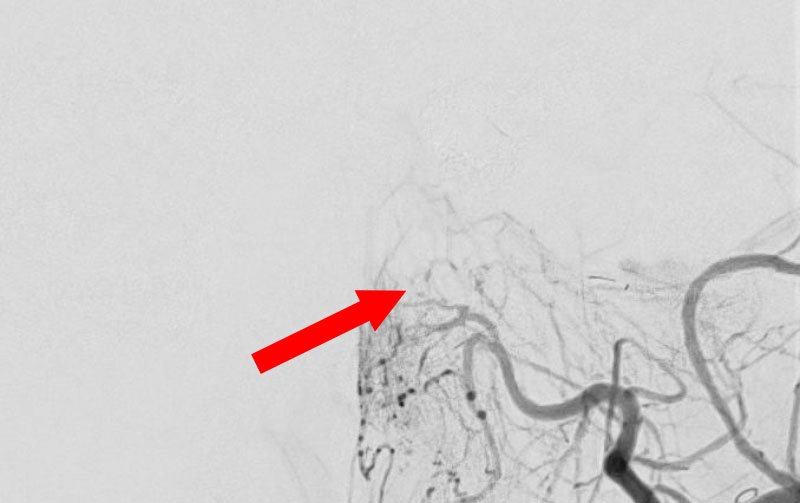

'25年10月

硬膜動静脈瘻

50代

救急外来

No.1591 手術前

No.1591 手術中

No.1591 手術後